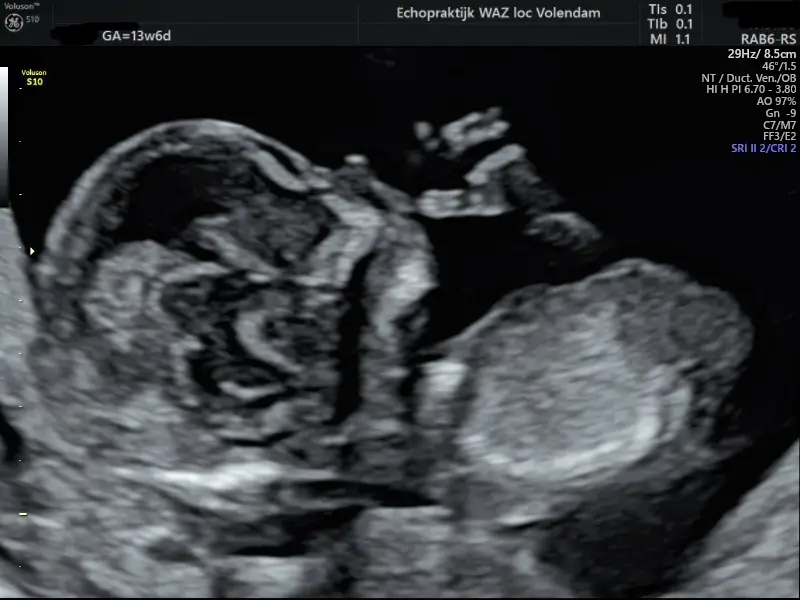

13 weken echo ( Eerste Trimester Structureel Echoscopisch Onderzoek)

Deze echo is de 1e belangrijke check bij je kindje. Deze echo vindt plaats tussen 12 + 3 weken en 14 + 3 weken.

Met deze echo kun je al vroeg in de zwangerschap laten onderzoeken of je kindje ernstige lichamelijke afwijkingen heeft. Zo heb je meer tijd om te bepalen wat je met de uitslag doet. Er wordt o.a. naar de schedel, het hart, de buik, de armen en benen, de wervelkolom, het vruchtwater, de nekplooi en de placenta gekeken.